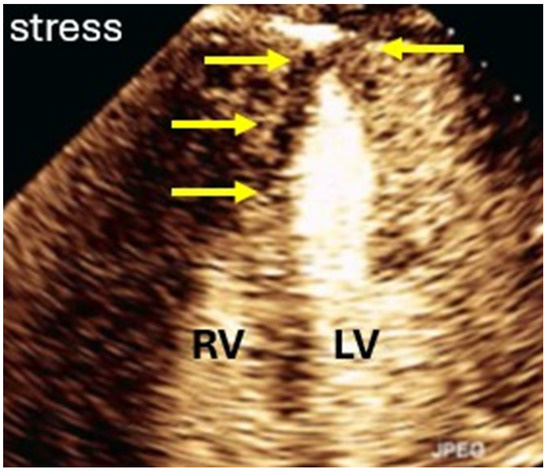

7.2.2. Pre-Assessment and Primary Scan Plane

7.2.3. CEUS Procedure

7.2.4. Pitfalls

7.3. Interpretation and Reporting

| Assessment of myocardial ischemia/viability during stress echocardiography |

| Imaging method | Low-MI-contrast-specific imaging—Flash–Replenishment |

| Typical findings | Normal myocardial perfusion: homogeneous opacification of the segment, contrast replenishment within 5 s after flash (2 s during stress) Abnormal perfusion: delayed contrast replenishment, perfusion defect, often combined with abnormal wall motion Tumors may show patchy opacification and include dark areas due to necrosis |